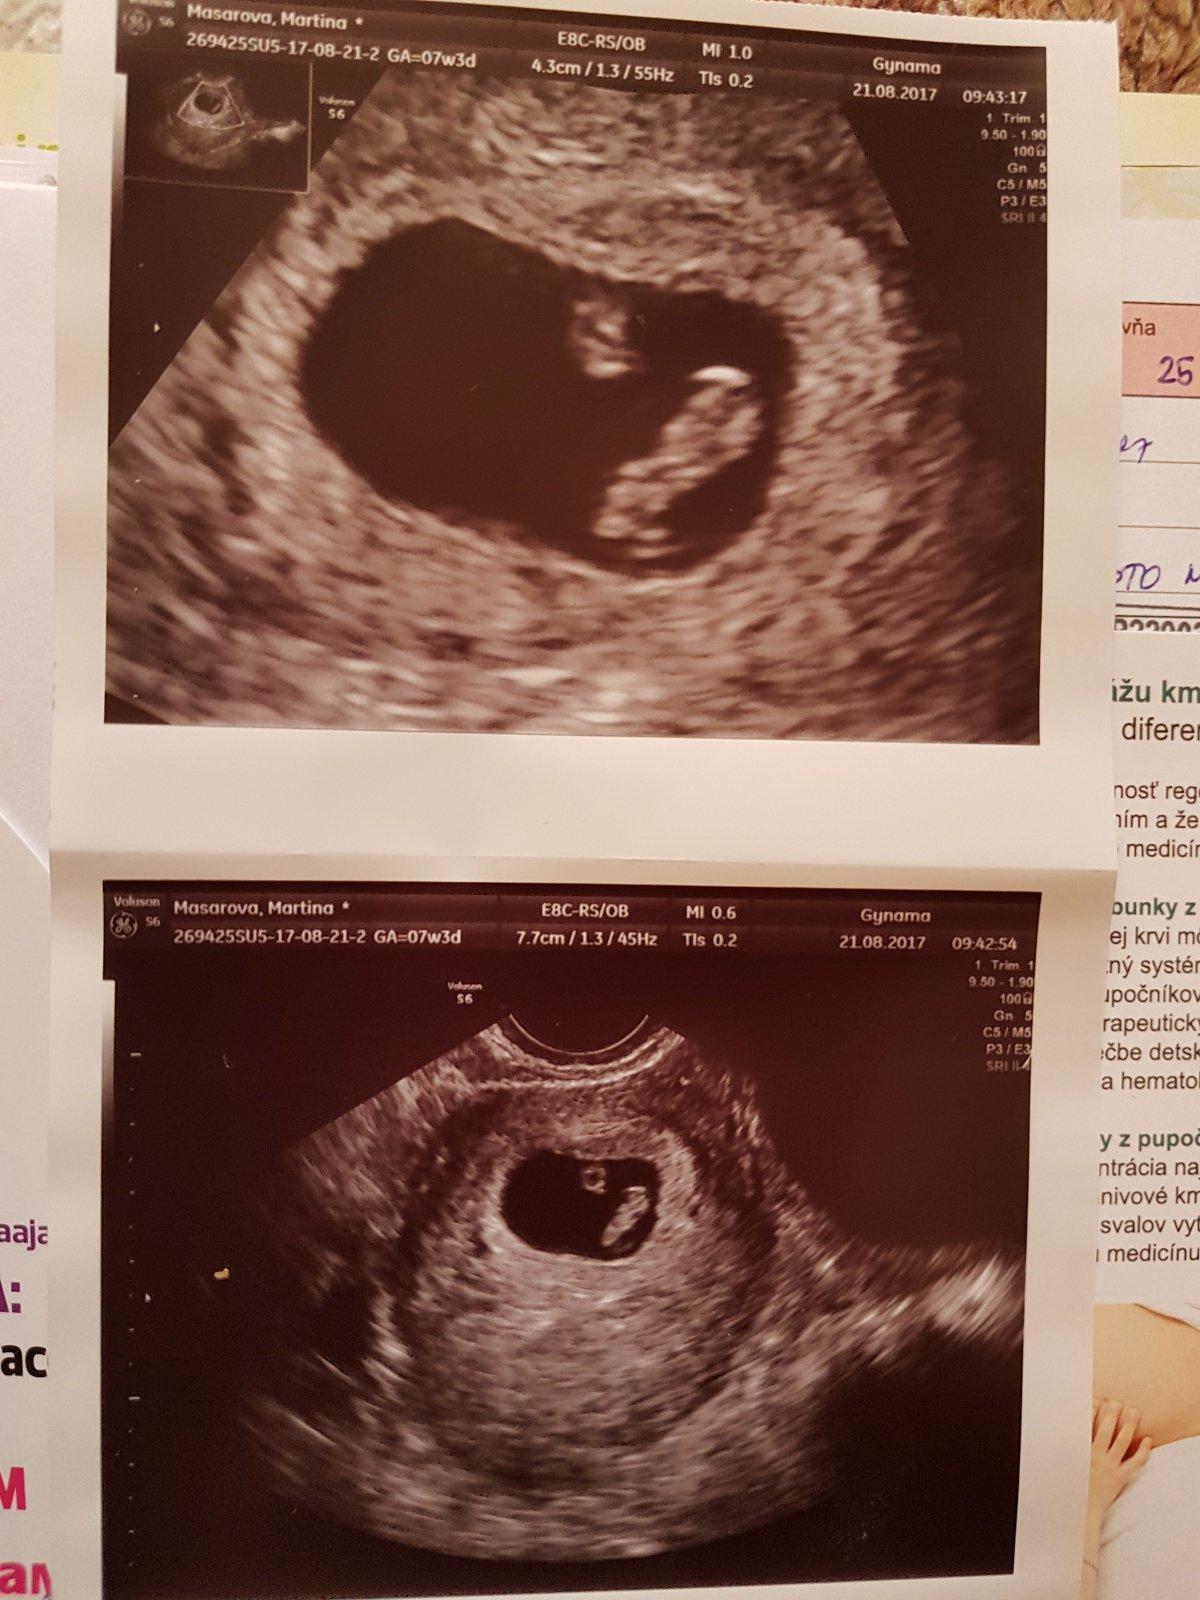

Gratulujeme Martinka😊Koľko meriate?

@lula313 dakujeme;) mame 11mm

@martinkamm ja som nevzdelana, ale preco su tam tie machulky dve? Hanbim sa spytat, ale babenko je ktora z nich? 😀

Yen to bude asi zltkovy vak

@yennn ja som to tiez nevedela nemusis sa bat 🙂vacsie je babatko a mensie zltkovy vak presne ako pise lula313 ;)